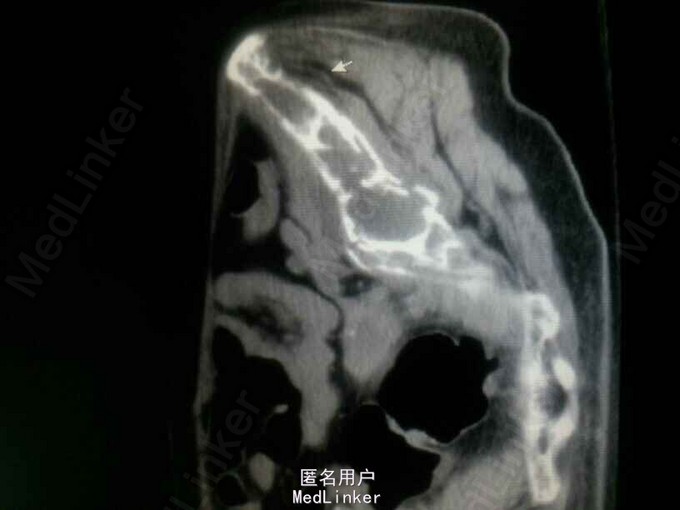

入院后查钾:2.63,钙:3.72,同时尿素氮14.23,肌酐140,碱性磷酸酶672。同时B超提示双肾多发结石。即考虑甲旁亢可能。行PTH:2143。基本明确确诊甲旁亢。但查双侧甲状旁腺B超正常。胸部增强CT提示主动脉弓旁软组织肿块影,双侧多发肋骨骨质破坏。甲状旁腺显像:左胸局部放射性异常摄取。 诊断:异位甲状旁腺肿瘤,甲旁亢,高钙血症,肾结石,病理性骨折。 予降钙等治疗后行剖胸纵膈肿瘤切除术

经随访血钙明显下降。 讨论:甲状旁腺亢进经药物治疗常常暂时有效,但是长远来看手术是彻底治疗的办法。随着时间长,骨钙溶解及高血钙会造成不同脏器的严重后果。定位办法包括99mTcMIBI显像,必要时可加做全身PET显像。值得一提的是肿瘤质软,非常脆,不韧,易撕裂,而且血供较为丰富。手术时需小心操作。本例胸腔镜亦可完成。为探查仔细,避免风险,与家属也协商过,还是剖胸手术